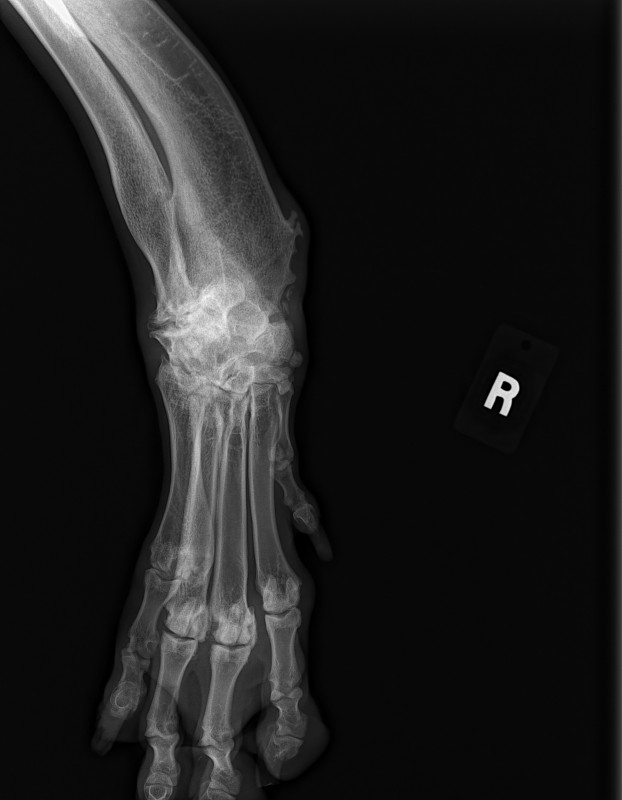

The current size of his mass is 8.2 cm x 10 cm x 21 cm. This is an extremely RARE cancer – less than 1%.

To further complicate matters, this mass has herniated down into his thigh and groin severely compromising his ureter and femoral nerve. He has had three CT scans of which his latest has shown that to date his chest remains clear of metastasis and his lymph nodes are not enlarged. His MRI has shown that his case is extremely complicated and the surgery he shall specifically require, scheduled for March 23rd has ONLY ever been done twice before by the two expert surgical oncologists assigned to him.